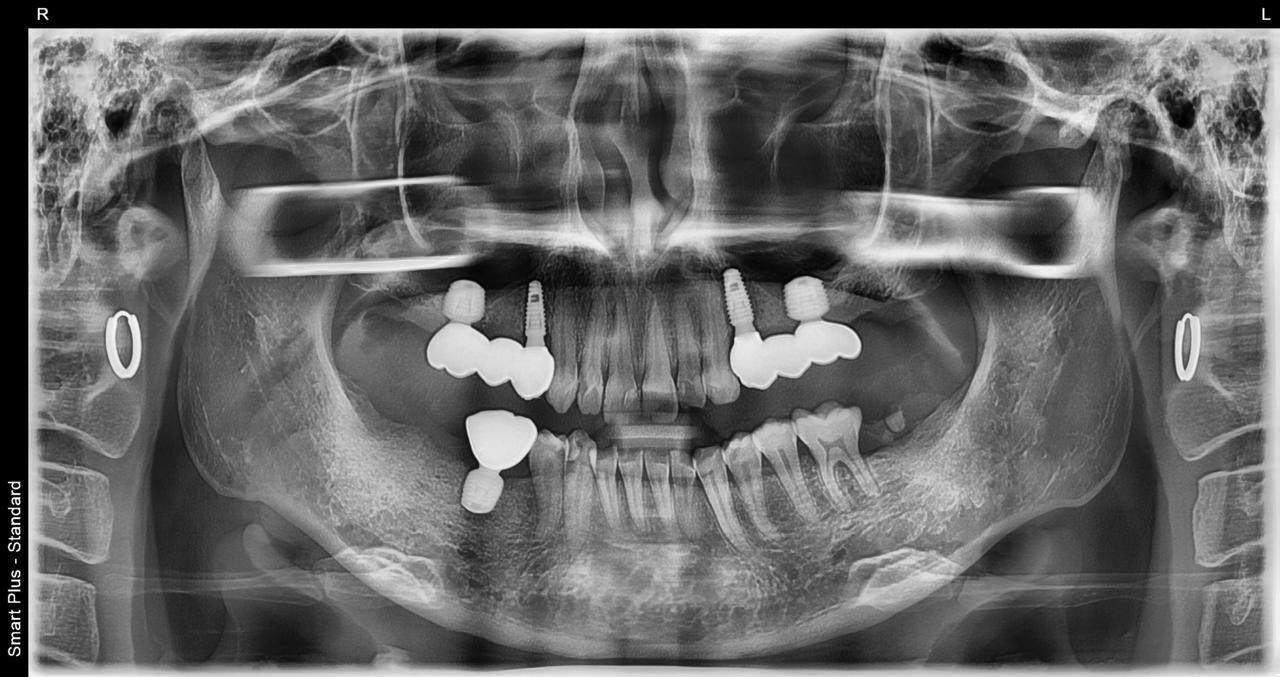

5.左上4番のインプラント抜歯即時埋入、左上6番の上顎既存骨1から2mmのグラフトレスサイナスリフト、左下56の大幅な骨欠損により、下顎神経の損傷を回避するために、ショートインプラントを使用し、左下56にインプラントを埋入し、最終補綴物は、左上456の3ユニットのジルコニアブリッジし、左下56は、ジルコニアの連結冠を装着したケース

Before

枚方市のインプラントの症例

After

M・I 様 女性 70代

症状としては、左下56は、歯周病で欠損したと考えられるが、かなりの骨欠損をともなっていた。左上456に関しては、動揺が大きく、炎症が起き、排膿、および、歯性上顎洞炎を起こしていた。

治療法としては、動揺がひどくなってきて、炎症の症状もあったため、左上56の抜歯を希望。インプラント治療をその後、希望したため、左上4に関しては抜歯即時埋入。左上6に関しては、既存骨1から2mmでインプラント治療が厳しい状態であったが、グラフトレスサイナスリフトを行い、治療期間5か月はかかるということを説明して、インプラント埋入をおこないました。その後、2か月半後、大幅に骨が欠損している下顎56に対して、ショートインプラントを使用して、下顎神経の損傷を避けて、インプラント埋入を終えています。その後2か月後に光学印象で印象を行い、上顎刺億456歯、3ユニットのジルコニアブリッジを装着。下顎左側56に関しては、骨欠損が大きいため、歯冠長がだいぶ長くなるため、ジルコニアの連結冠を装着して治療を終えた。

治療結果は、上顎6に関しては、既存骨が少なく、厳しい治療ではありましたが、5か月で治療を終え、患者様の負担を最小限に抑えるができたと考えます。(従来のサイナスリフトでは、このようなケースでは1年以上、1年程度の治療期間がかかるか、治療が不可能と言われるケースだと考えます。)また、下顎は骨欠損が大きく、下歯槽管のリスクが起きることが考えられますが、ショートインプラントを使用することで安全に治療を行うことができました。

治療の期間・回数:治療期間5か月(上顎456 3ピースブリッジの治療は5か月(上顎既存骨が2mm程度しかなく、骨結合に時間がかかるケースであったために、5か月の治療期間が必要であった。)(左下56に関しては2か月半で治療を終えています。)治療回数は、13回。

治療の価格:1,474,000円(税込)

治療費の内訳:左上46および左下56のインプラント基本料(フィックスチャー及び手術費用、投薬費用、レントゲン費用、インプラント上部費用(アバットメントおよびジルコニアクラウンの費用用)330000円(税込み)×4本分 1320000円(税込)。左上5ジルコニアポンテック費用88000円(税込)。オプション費用、左上4抜歯即時埋入加算(人工骨費用を含む)+グラフトレスサイナスリフト費用 33000円(税込)、左上6グラフトレスサイナスリフト費用 33000円(税込)

治療のリスクや副作用:手術後に、痛みや腫れ、出血、合併症などを引き起こす可能性があります。噛む感覚がご自身の歯と異なる場合があります。見た目がご自身の歯と異なる場合があります。手術後にメインテナンスを継続しないと、インプラントが抜け落ちる可能性があります。